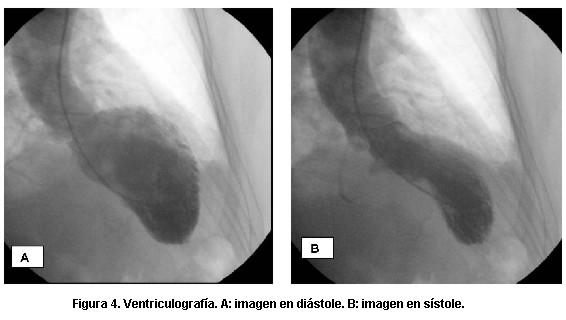

Figura 5. Coronariografía. A: coronaria derecha. B: coronaria izquierda (descendente anterior y circunfleja).

Presentamos un caso clínico en el que se consideró como posible diagnóstico la miocardiopatía de takotsubo. Se trata de una paciente de 64 años, hipertensa, que consulta en emergencia por angor de reposo, prolongado, asociado a situación de estrés psíquico. Del examen físico del ingreso se destaca: paciente lúcida, eupneica, tolera el decúbito, bien hidratada y perfundida. Examen cardiovascular: ritmo regular de 70 cpm, ruidos bien golpeados, silencios libres, presión arterial 140/90 mmHg. Examen pleuropulmonar: buena entrada de aire bilateral, no estertores. En el electrocardiograma (ECG) del ingreso (figura 1) se objetivaba taquicardia sinusal de 110 cpm, P y PR normales, eje a aproximadamente -40 grados, ondas Q patológicas en cara anteroseptal, ascenso del segmento ST de V2 a V4, QT 0,38 s. Se administran nitritos sublinguales, cede el dolor y renivela el segmento ST (figura 2). El test de troponinas fue negativo. La paciente fue dada de alta a domicilio con ácido acetilsalicílico (AAS), betabloqueantes y pase a cardiólogo. A los cuatro días consulta por nuevo episodio anginoso. El ECG de ese momento muestra elementos sugestivos de isquemia subepicárdica extensa (figura 3). El enzimograma cardíaco fue negativo. Se inició tratamiento en base a AAS, heparina de bajo peso moleculary nitroglicerina, con lo que cede el dolor. Se realizó un ecocardiograma que evidenció hipoquinesia apical y disminución leve de la fracción de eyección del ventrículo izquierdo. En la cineangiocoronariografía realizada de urgencia se informó ausencia de lesiones coronarias significativas; hipoquinesia severa anterior y apical (figuras 4 y 5). La paciente evolucionó asintomática. Se confirmó ecocardiográficamente la recuperación de la motilidad y función ventricular en el plazo de un mes